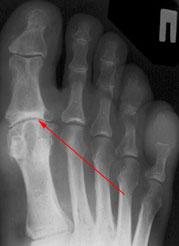

Для диагностики обязательно необходимо провести рентгенографию стопы. Этот метод позволяет выявить костные изменения, разрастания, пограничные дефекты суставных поверхностей, уменьшение суставных щелей, субхондральный склероз костной ткани и наличия кистовидных образований, что дает возможность провести дифференциальную диагностику.

На третьей степени боли становятся постоянными и беспокоят даже в состоянии покоя. Тыльное сгибание пальца отсутствует, подошвенное ограничено. Возникает деформация сустава. На рентгенографических изображениях фиксируются костные наросты, выраженная деформация суставных поверхностей.